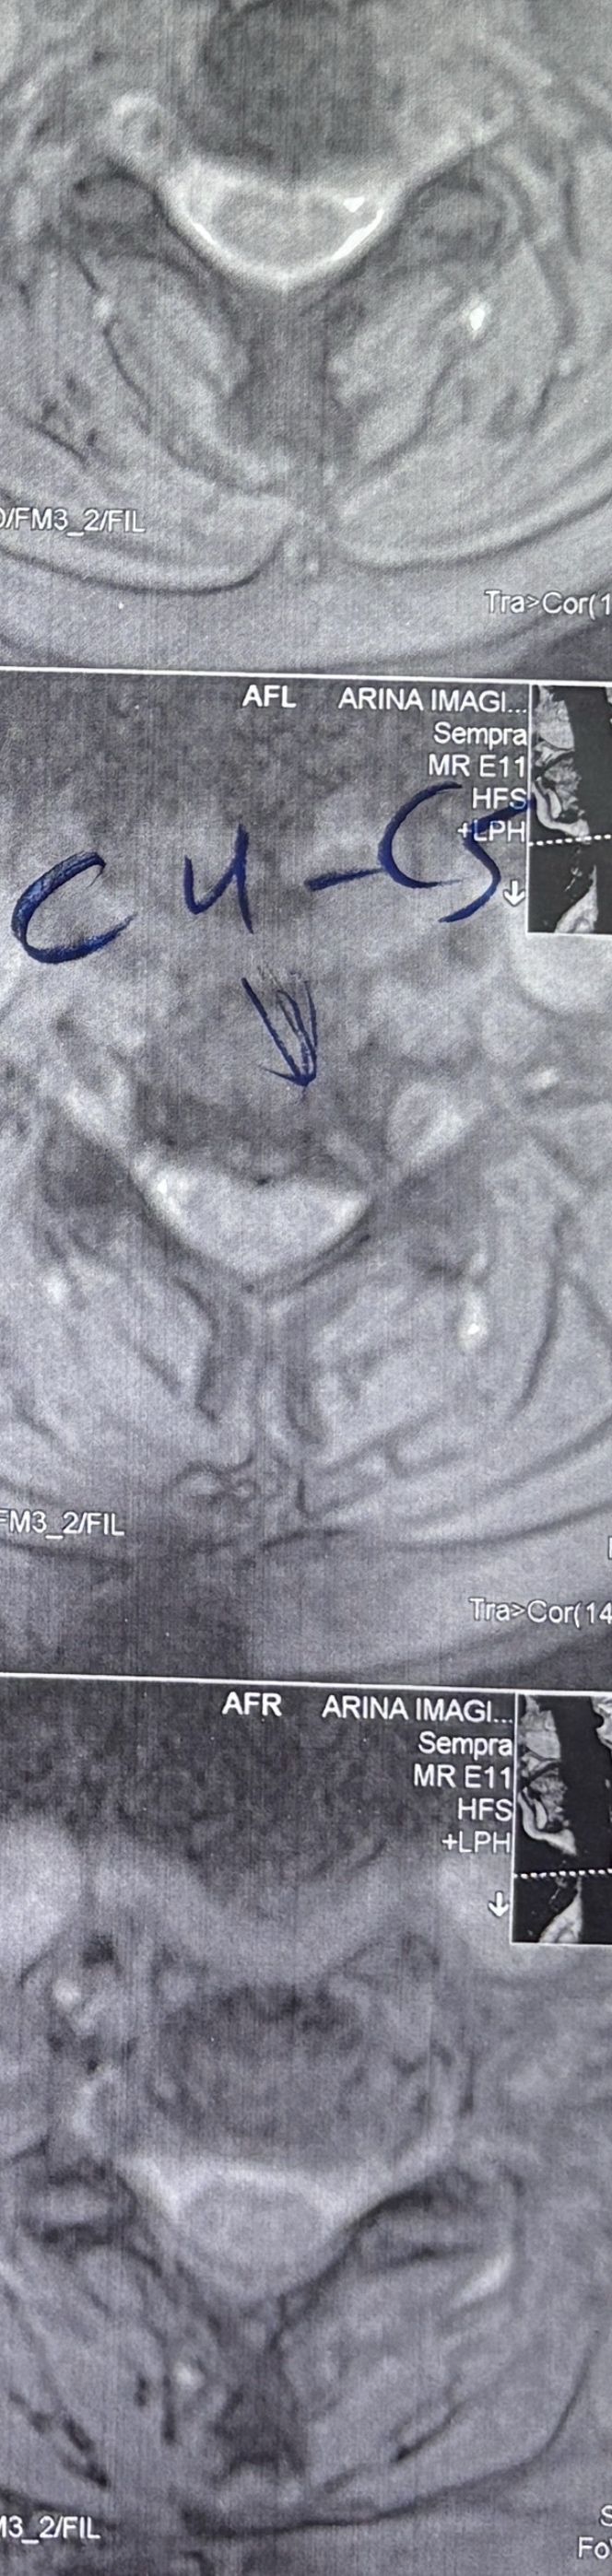

41 years old man presented to my clinic in October 2023 with acute and sever R neck pain with radicular pain to his R upper extremity along C6 dematom since 2 weeks ago. Examination didn’t show any upper motor signs. Was suggested urgent surgery

I ordered EMG/ NCV : showed mild R C6, C7 irritation without any active axonal loss

In his MRI was reported R. para R. IVF Massive extrusion. I decided to control his pain and manage this patient with reevaluation of patient every other session. For 5 sessions i just used acupuncture and laser and IFC and mild adjustments to his R. T3-T7 and mild arthosteem to above and below involved segment. Cervical adjustment considered contraindicated for this patient. From session 6th- 8th i started to use mild/gentle cervical decompression. He used soft cervical collar all the time. His pain decreased by 80 percent

I gave him cervical traction pump to be used 3-5 times per day at home for the next 3 months and i released the patient. He was evaluated every week once for one month and after that every 2 weeks. After 3 month I repeated MRI. Size of the herniated disc was reduced greater than 50 percent. Asked him to do another mri in 6 months

MRIs before and after proper management of this patient: